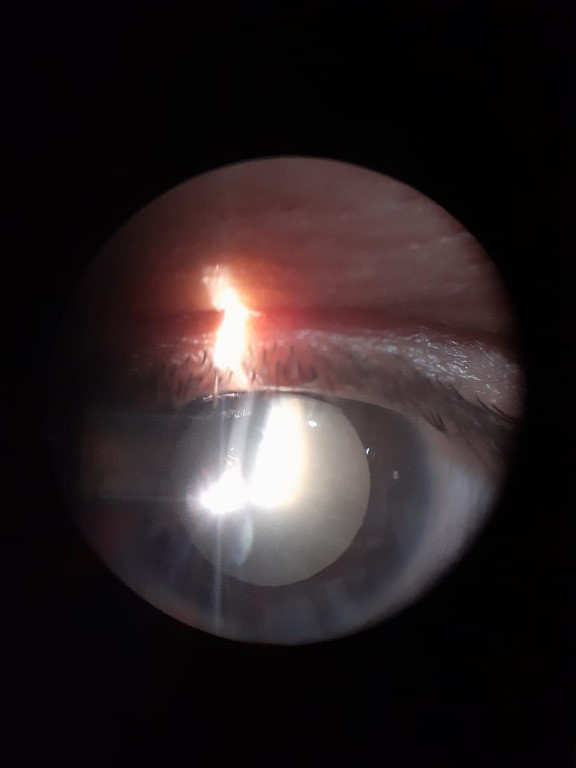

Casos Clínicos

Envíado por Dr. José Alfredo Martínez